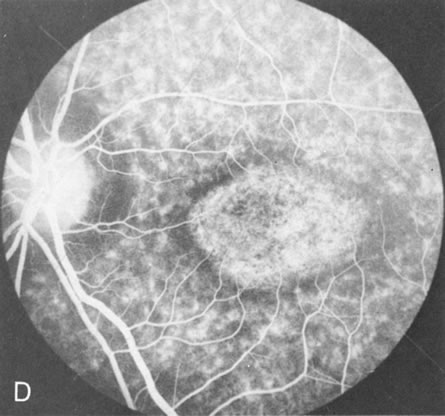

Generalized choroidal dystrophy is usually noted in middle-aged mildly symptomatic individuals who show a predominantly peripapillary or pericentral distribution of choroidal atrophy. Gradually, over the years these areas enlarge to eventually involve the entire retina. These changes are vividly seen on FA (Fig. 6).

Fig. 6. Generalized choroidal dystrophy. This 65-year-old woman gradually developed enlarging, progressive areas of choroidal atrophy over a 20-year period. When initially seen, the abnormalities were confined to the peripapillary and macular region (A,B). In a recent examination, the generalized choroidal atrophy is vividly demonstrated on angiography (C–F).